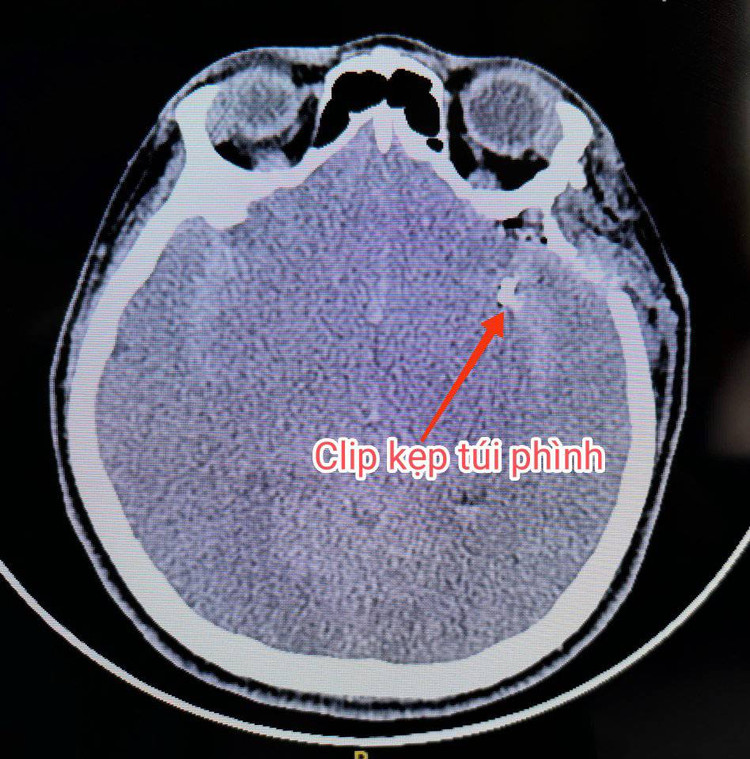

| Clip kẹp túi phình mạch máu não - Ảnh BVCC |

Sau khi hội chẩn và cân nhắc các nguy cơ, ca phẫu thuật được thực hiện bởi BS. CKII. Trương Thái Dương cùng ekip các bác sĩ Khoa Sọ Não Cột Sống 1. Sau 3 giờ phẫu thuật căng thẳng, cẩn trọng trong từng thao tác, túi phình mạch máu não đã được kẹp và kiểm soát hoàn toàn. Hiện tại, tình trạng sức khỏe bệnh nhân đã ổn định, không còn đau đầu, tay chân vận động tốt.

Theo BS.CKII Trương Thái Dương, Trưởng Khoa Sọ Não Cột Sống 1 BVĐK Xuyên Á cho biết: “Đây là một trường hợp khó, túi phình có kích thước lớn, cổ rộng, nằm ở vị trí không thuận lợi, nguy cơ vỡ cao, ranh giới giữa sự sống và cái chết chỉ trong tích tắc.

Nhưng với kinh nghiệm vốn có, bác sĩ cùng ekip đã khống chế thành công cổ túi phình, loại bỏ hoàn toàn nguy cơ tái vỡ. Sau phẫu thuật bệnh nhân tiếp tục được điều trị tích cực, kiểm soát các biến chứng do xuất huyết dưới nhện, phối hợp điều trị vật lý trị liệu và đã hoàn toàn hồi phục.”